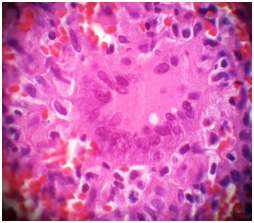

Figure 4 Show Giant cell in the granulomas.

Figure 6 A necrotizing granuloma H& E X 400.